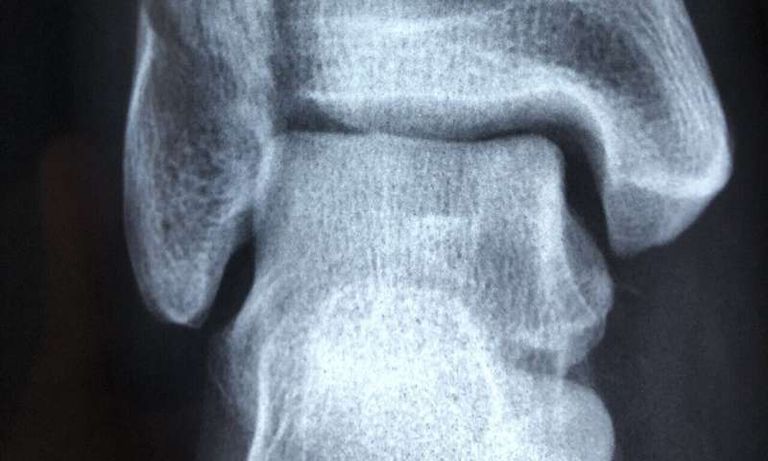

وحلل فريق بحثي من جامعة نيفادا نحو 30 ألف حالة كسر في العظام تم الإبلاغ عنها على مدار العقود الثلاثة الماضية في 27 منشورًا بحثيًا، ووجدوا أن التدخين يزيد من خطر كسر العظام بنسبة تصل إلى 37%.

ويعد هذا التحليل، الذي نُشر الأسبوع الماضي في مجلة "ساينتفيك ريبورتيز"، هو الأول الذي وسع فيه العلماء نطاق البحث إلى ما بعد فحص كسور الورك في المقام الأول إلى أجزاء أخرى من الجسم، بما في ذلك الرسغين والكتفين والساعدين وعظم الفخذين والساقين والعمود الفقري .

وتدعم دراسة جامعة نيفادا البيانات من الدراسات السابقة، التي وجدت أن التدخين يزيد من فرصة الإصابة بكسور العمود الفقري والورك لدى الرجال إلى 32% و 40% على التوالي.